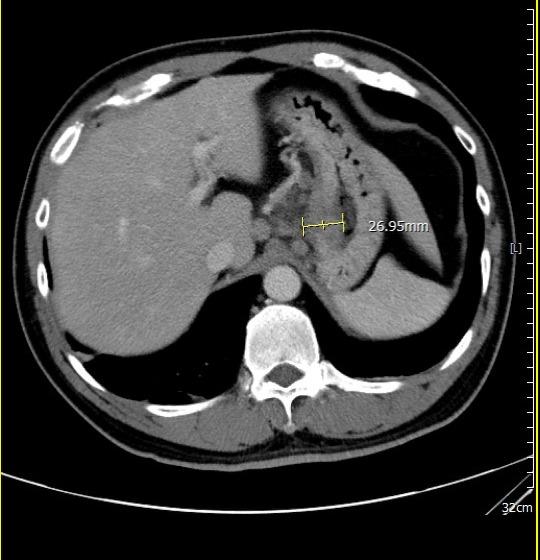

【記者吉雄世/高雄報導】53 歲男子因持續胃痛、食慾下降而日漸消瘦,至義大癌治療醫院血液腫瘤科饒坤銘副院長門診求診。原以為只是常見的腸胃不適,經檢查後,診斷第三期胃癌,腫瘤已明顯影響胃部功能,短短時間讓他體重減輕 10 公斤。突如其來的噩耗,讓病人與家屬瞬間陷入巨大的焦慮與無助。

饒坤銘醫師向家屬逐一說明疾病情況與治療計畫。饒醫師建議採用國際間日益普及的「免疫治療合併化學治療」術前療法。此治療方式可提前觀察藥物反應、協助縮小腫瘤,並有助於降低手術風險,讓原本低迷的家庭重新看見希望。

過去胃癌治療多以手術後化療為主,但近年研究已證實,術前治療能有效提升腫瘤可切除率。若術後病理組織中「完全找不到癌細胞」,稱為「病理完全反應」,通常與更低的復發風險及更理想的長期預後相關,已成為國際高度重視的治療指標。

經義大醫療外科團隊進一步評估後,患者體況已達手術標準,並順利接受胃部腫瘤切除手術。手術後的病理報告更帶來令人振奮的結果:腫瘤組織中未發現殘存癌細胞,成功達成「病理完全反應」。得知結果的當下,患者與家屬喜極而泣,醫療團隊也深感欣慰,這不僅是治療上的成功,更是病人、家屬與醫療團隊共同努力的成果。